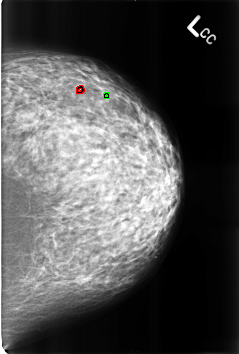

B_3178_1.LEFT_CC

FILE: B_3178_1.LEFT_CC.OVERLAY

TOTAL_ABNORMALITIES 2

ABNORMALITY 1

LESION_TYPE CALCIFICATION TYPE LUCENT_CENTER DISTRIBUTION N/A

ASSESSMENT 2

SUBTLETY 3

PATHOLOGY BENIGN_WITHOUT_CALLBACK

TOTAL_OUTLINES 1

BOUNDARY

ABNORMALITY 2